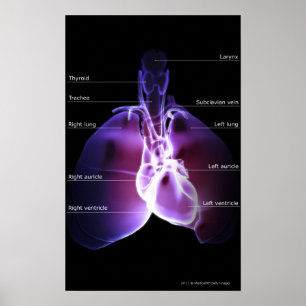

Hjärtans och lungornas struktur poster

Pris343,00 kr

Diagram över andningssystemet och hjärtat poster

Pris343,00 kr